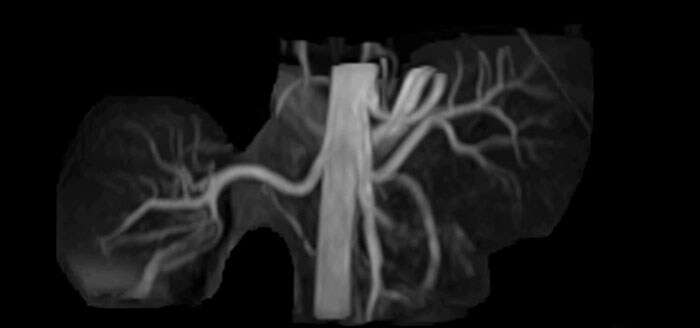

Imaging the renal arteries without contrast agent on Prodiva 1.5T.